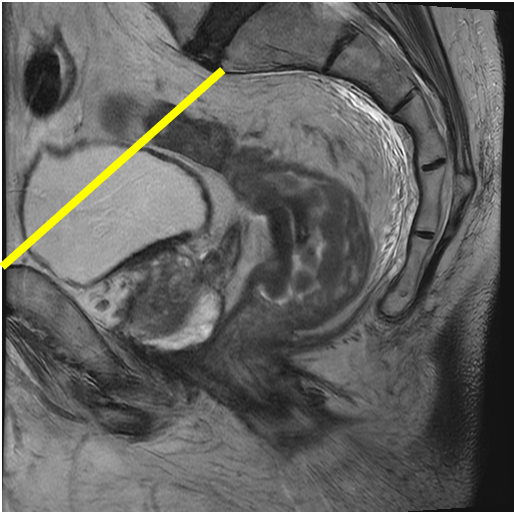

The proximal limit of the rectum can be defined in various ways. NCCN defines the rectum by the intestine that lies below the line that can be drawn between the sacral promontory and the upper edge of the pubic symphysis. Both these structures can be seen easily on magnetic resonance imaging (MRI; Figure 3).[2]